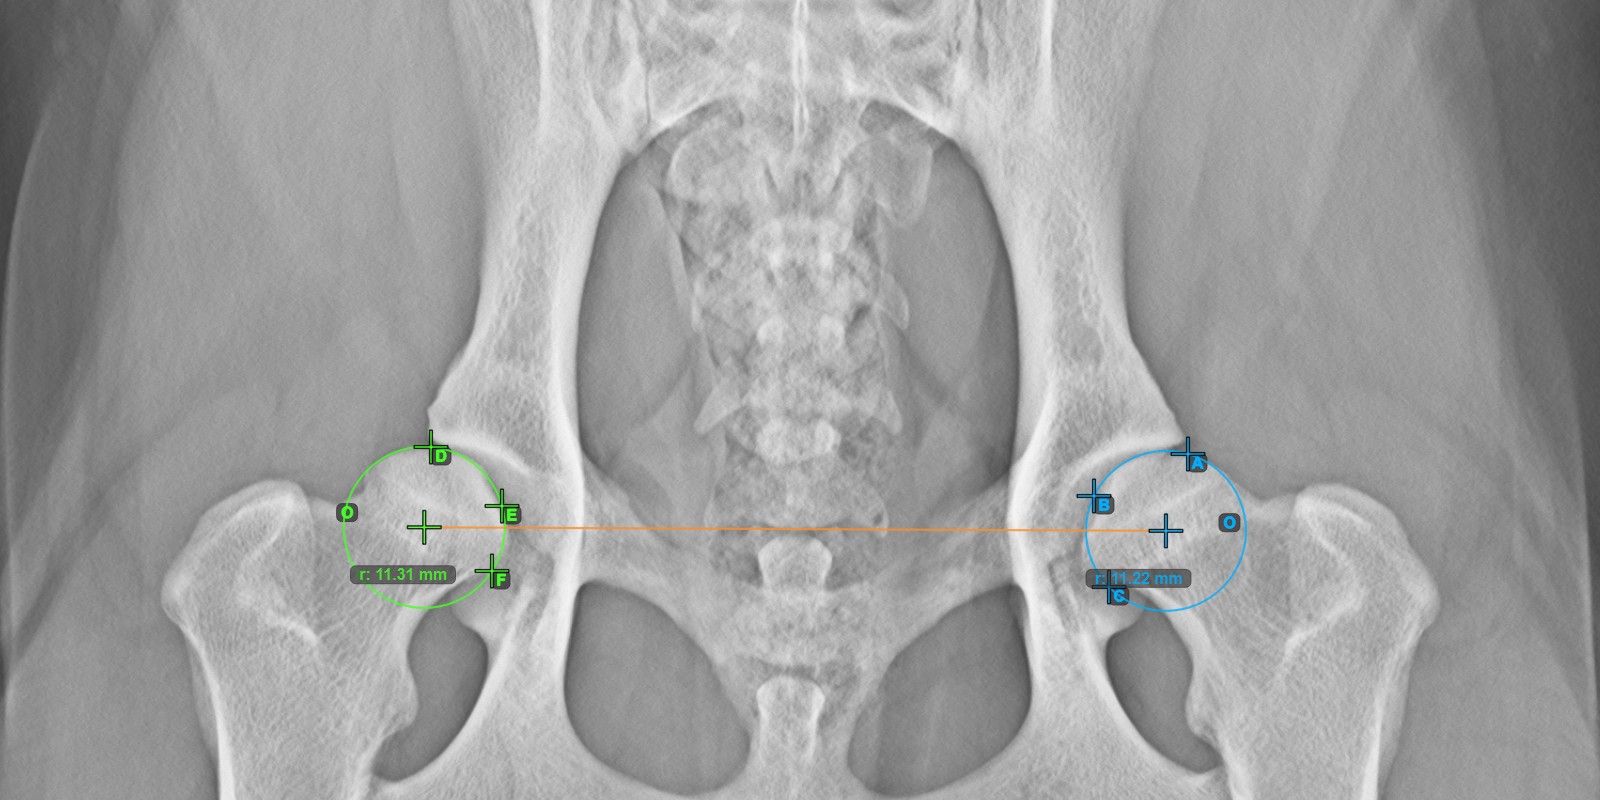

A lenti kép a **jobb* Caput Femoris ízületi felszínén elhelyezett három pont tipikus elhelyezkedését ábrázolja.*

../../_images/image100.jpg